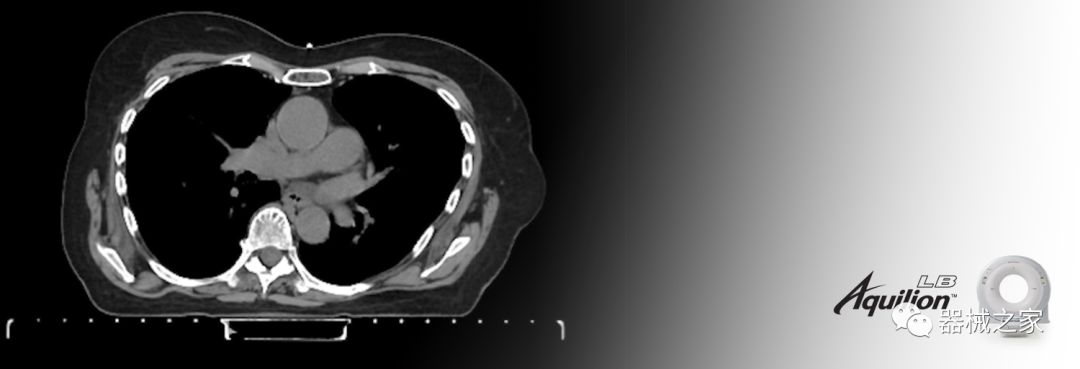

佳能醫(yī)療的Aquilion Lightning 80掃描儀還以緊湊,經(jīng)濟的包裝提供高質(zhì)量的成像。Aquilion Lightning 80旨在可靠,高效地運行,在繁忙的環(huán)境中生成高質(zhì)量的圖像。

Aquilion LB專為滿足腫瘤學挑戰(zhàn)而設(shè)計,同時優(yōu)先考慮患者護理。Aquilion LB的內(nèi)徑為90 cm,能夠幫助復雜的患者設(shè)置并提高患者的舒適度。CT模擬定位可以輕松鏡像放射治療定位,更加自信。該系統(tǒng)采用0.5 mm x 16排(32層)PUREViSION探測器技術(shù),70 cm視野,AIDR 3D和SEMAR技術(shù)。